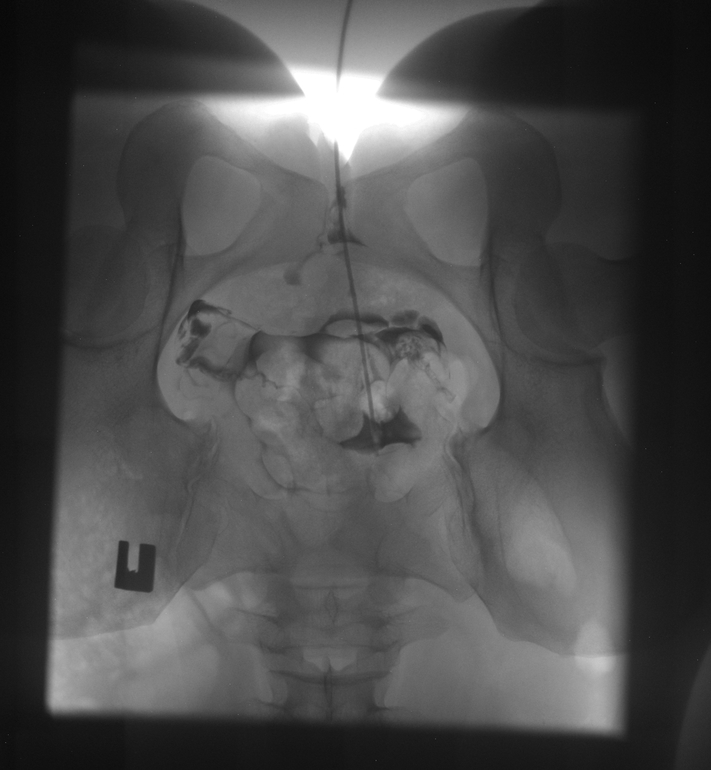

Моя ГСГ (МСГ)

ГСГ, ЭХО, МСГ, ФертилоскопияНу что, девочки, сегодня прошла я эту процедуру, такую долгожданную еще с марта.

Результат: идеально проходимые трубы, матка без патологий !

Таких идеально проходимых труб по словам гинеколога он давно не видел.

Только влил раствор, он сразу прошел. Влил- прошел. И так три раза.

Матка почему то отклонена чуть влево, без видимых причин .